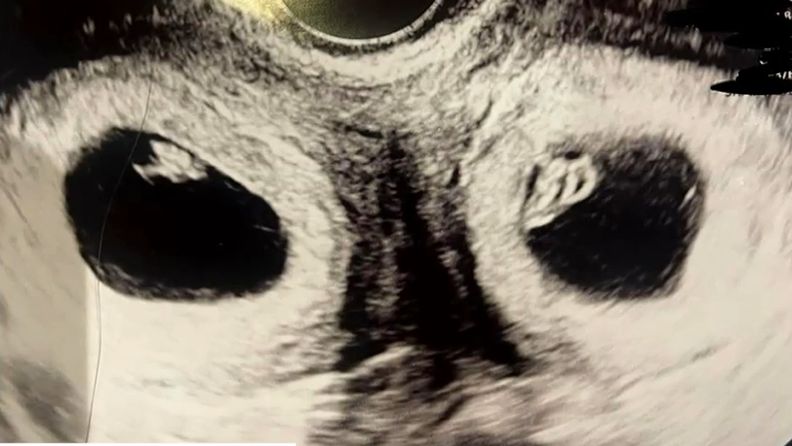

醫生建議她可以做試管嬰兒試試看,終於在2年9次的嘗試後成功懷孕,沒想到醫生幫她做產檢時,驚訝發現她懷上了雙胞胎,而且兩邊子宮還同時懷孕,最離奇的是,一邊是試管嬰兒,一邊是自然受孕,這種機率只有5千萬分之一!

(圖片來源:9now.nine.com.au)